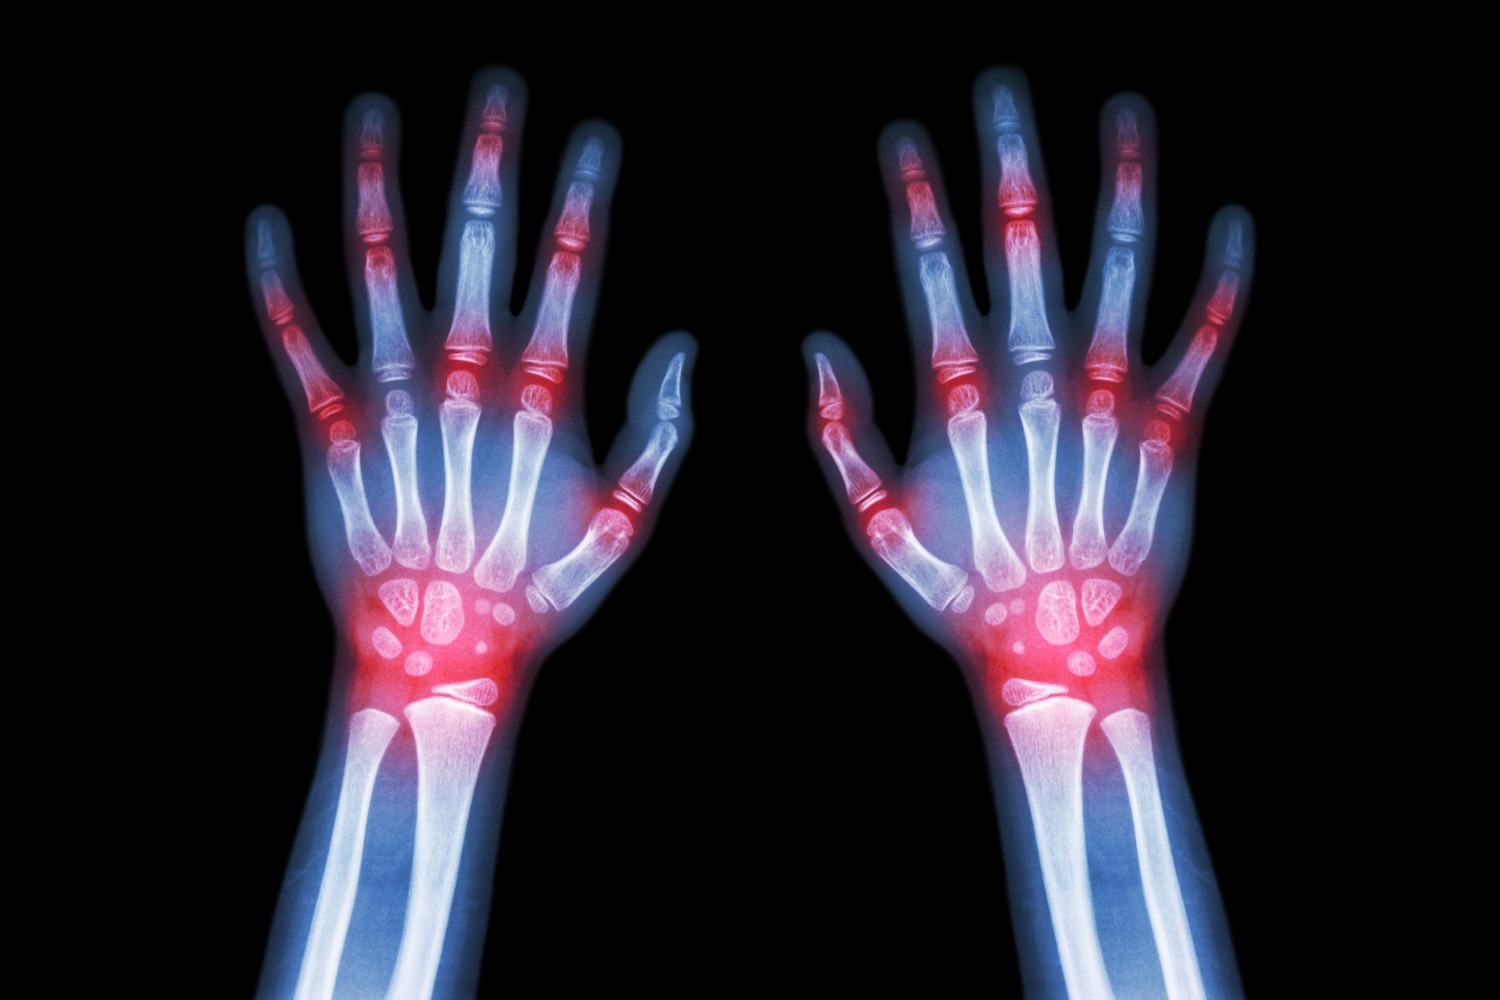

Symptoms of Juvenile Idiopathic Arthritis

Different forms of arthritis can present different symptoms. However, some common symptoms seen in children that can tip off a parent that there is an issue to look into are:

- Pain in the joints

- Stiffness

- Swelling in one or multiple joints

- Inability to carry out regular physical activities or play sports

- Heat around the affected joints

- Fatigue

- Fever

- MRI scans

- Ultrasound

- X-rays